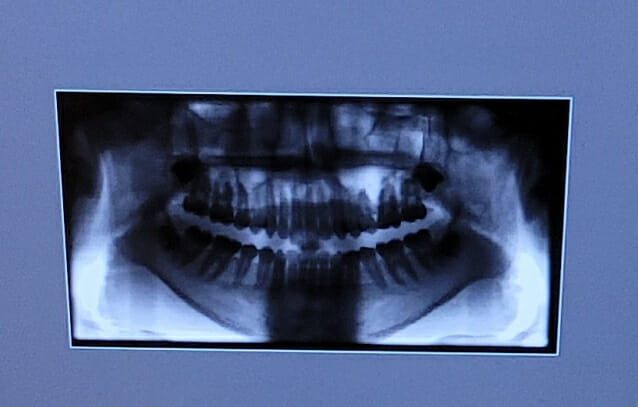

골다공증 치료제 투여 환자, 발치 후 턱뼈 괴사 위험

[지디넷코리아] 골다공증 치료제를 투여하는 환자의 경우 발치 후 턱뼈 괴사 위험이 높아지는 만큼 약물 중단을 고려해야 한다는 연구가 발표됐다. 분당서울대병원 내분비대사내과 공성혜 교수와 치과 이효정 교수팀이 골다공증 치료제의 […]